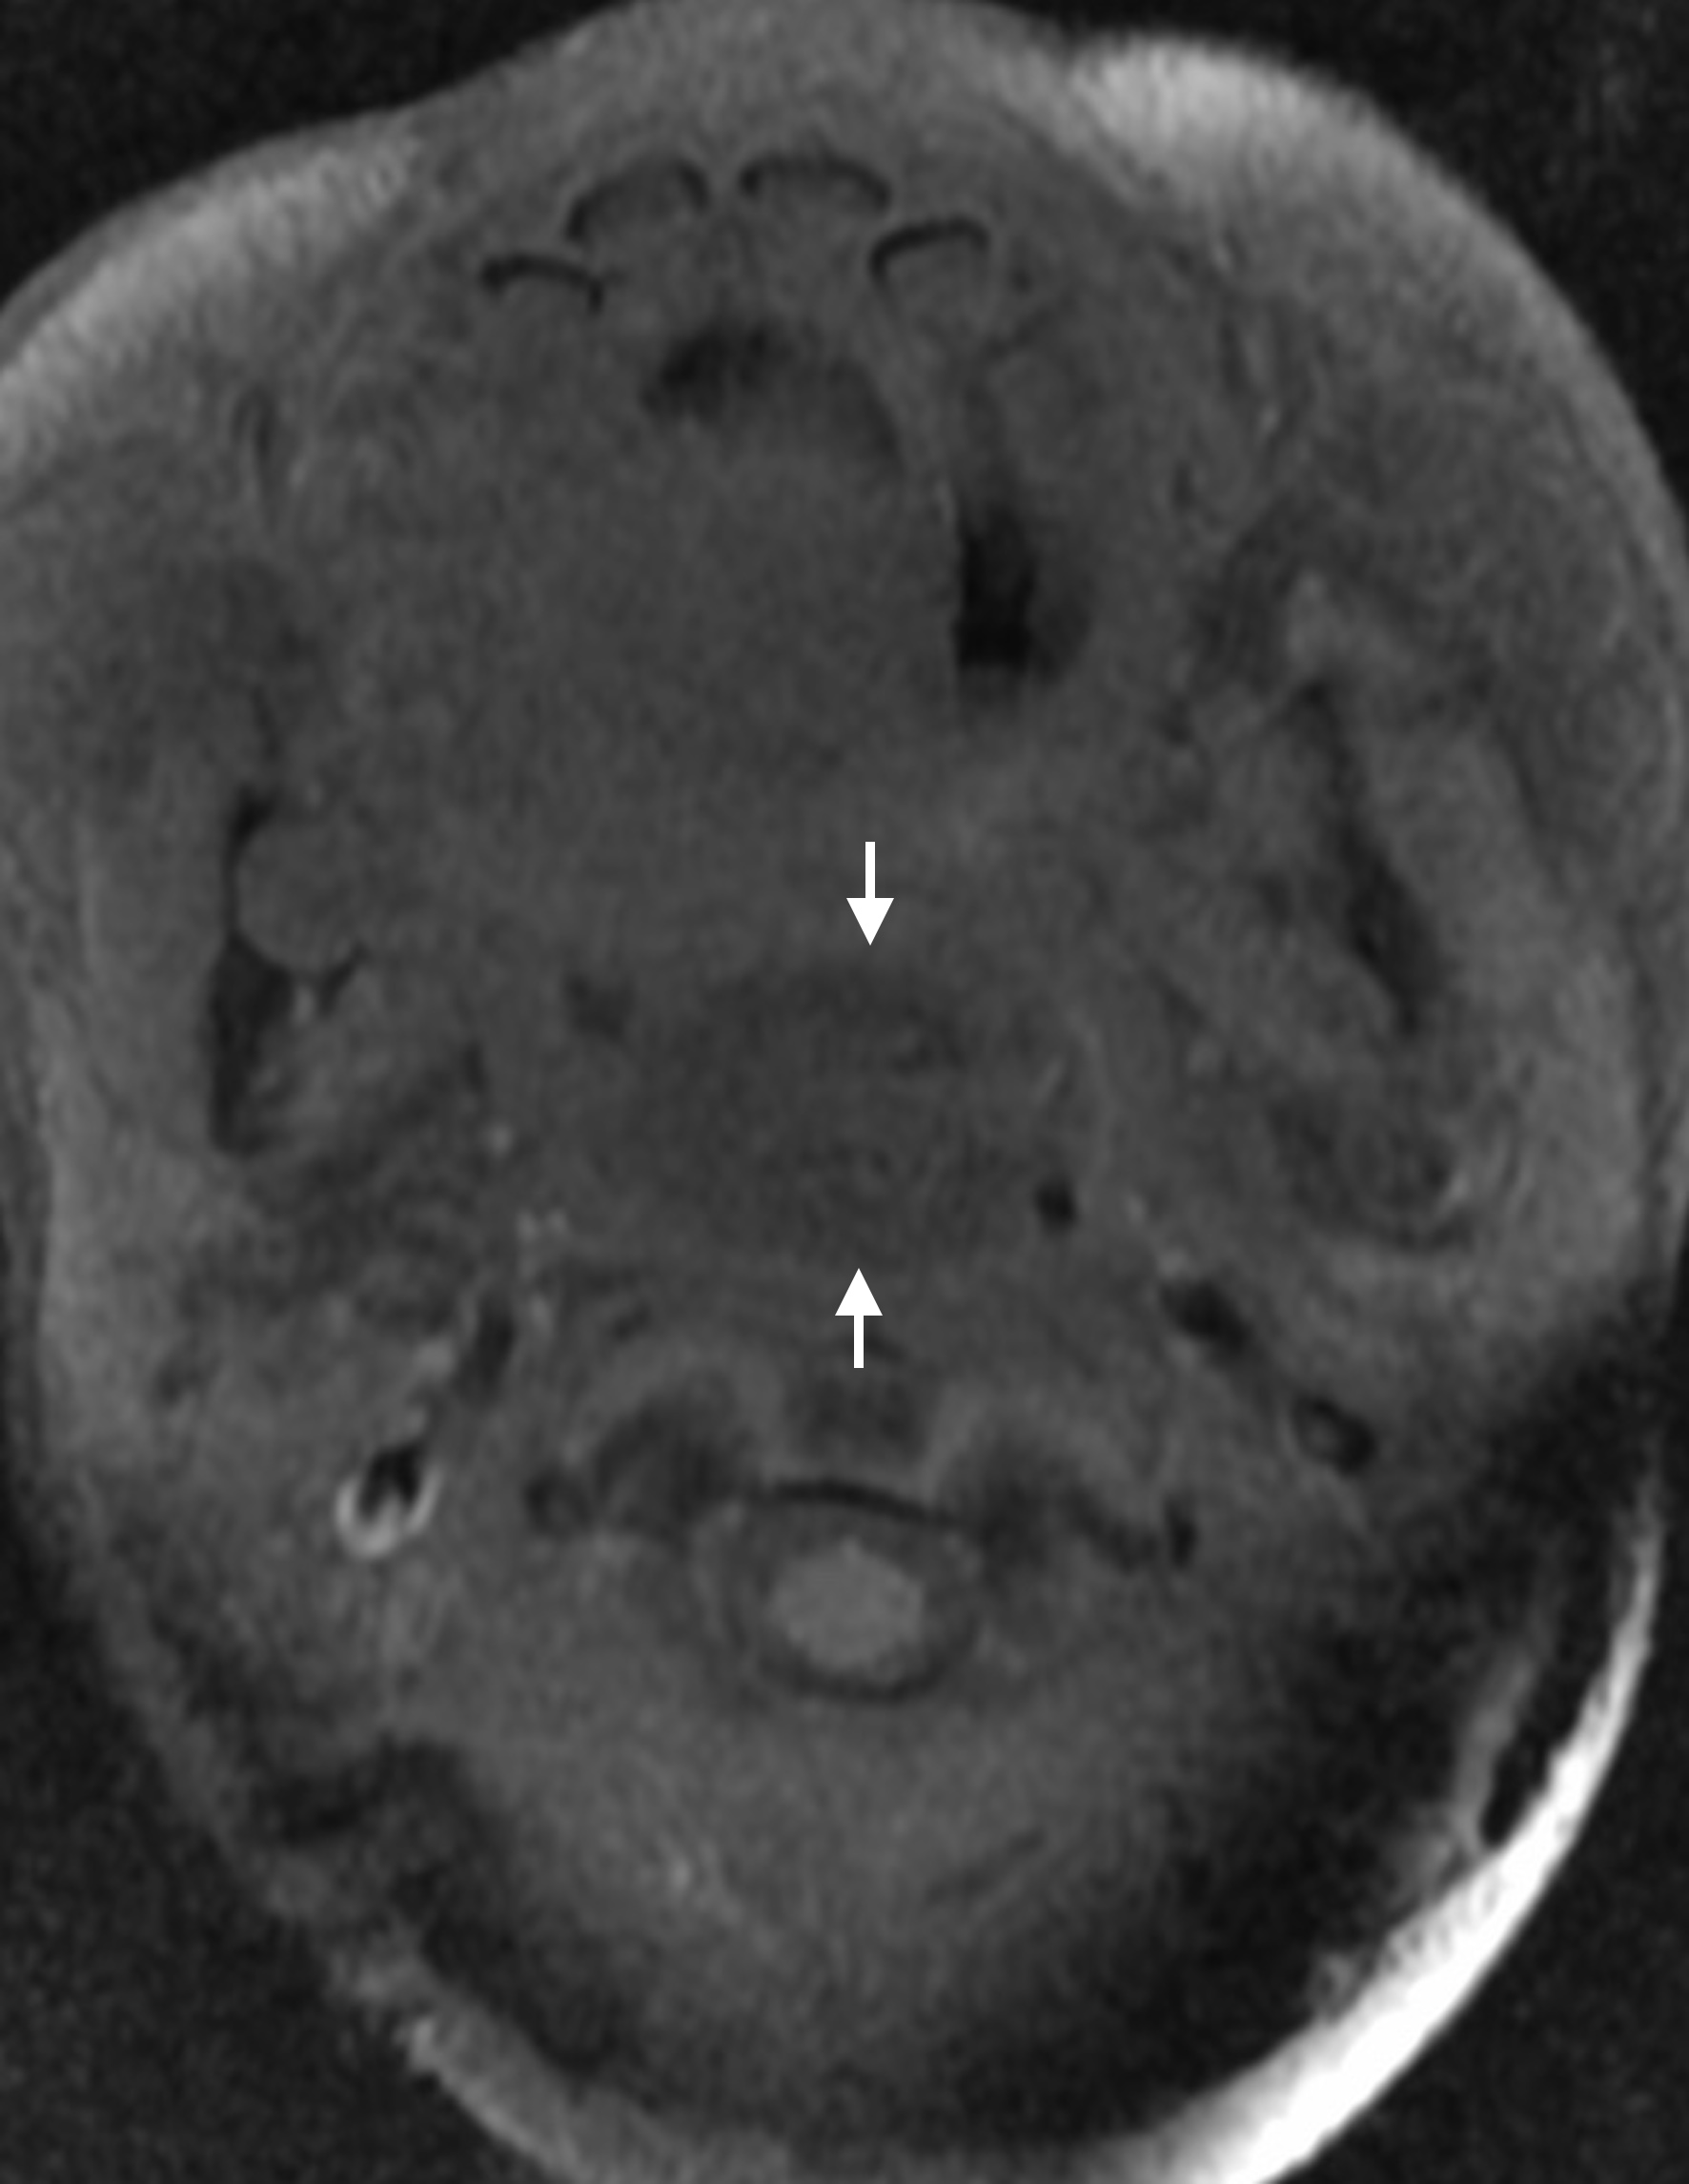

Pharyngeal hairy polyps are rare lesions that arise from the nasopharynx or oropharynx. It occurs predominately in females, with predilection for the left side. Its etiology remains poorly understood. It typically presents in the neonatal period with respiratory distress and feeding difficulties. Imaging is fundamental to identify the high fat content of the lesion. Surgical resection is the treatment of choice. We report a case of a nasopharyngeal hairy polyp causing respiratory distress since birth.